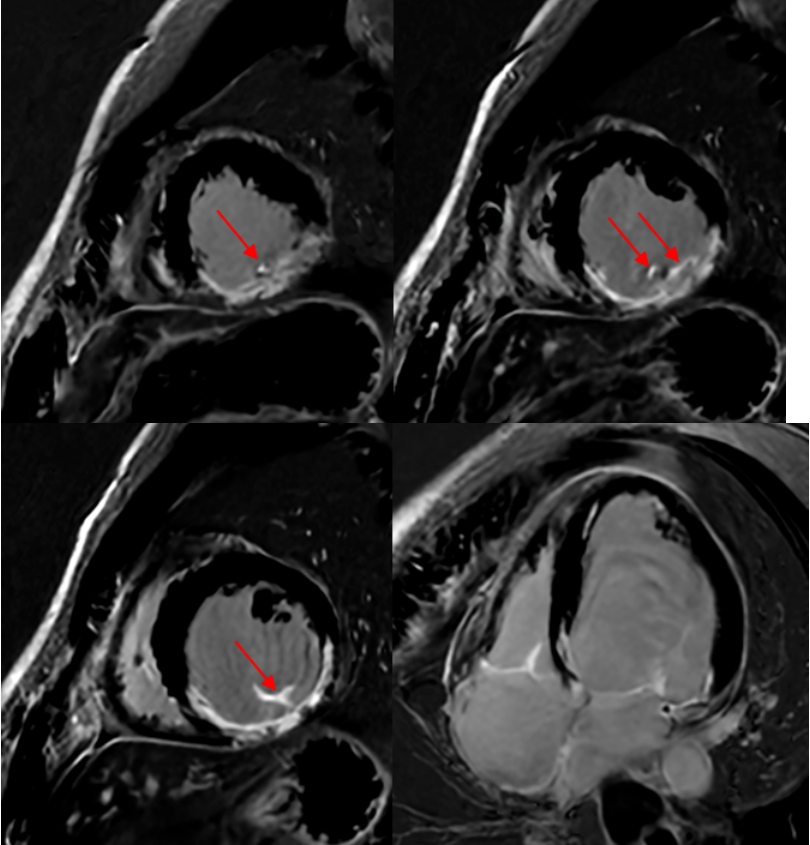

SA PSMDE(常规傅里叶变换重建)进一步提示下间隔壁,下壁,下侧壁延迟强化,范围超过心肌厚度的50%,提示患者透壁性心肌梗死。这时候,有必要结合病史,理性反推求医过程: 主诉:心脏术后1年余,活动后胸闷1年。 现病史:缘于入院前1年余因“二尖瓣关闭不全”于外院行“二尖瓣成形”,术顺,术后规律服药,1年前无明显诱因出现胸闷、气促,爬3层楼即出现症状,休息后稍缓解,无胸痛、心悸,无端坐呼吸、咳粉红色泡沫样痰、无夜间阵发性呼吸困难,无腹胀、眼黄、尿黄、肢体浮肿,无畏冷、发热、无黑膘、晕厥,无食欲减退、消瘦,就诊外院完善相关检查后诊断“心力衰竭”,予诺欣妥、信他乐克、螺内酯、达格列净等药物治疗,上述症状仍反复发作,今为进一步治疗就诊我院查心脏彩超:二尖瓣成形术后;二尖瓣轻度返流,左室收缩功能重度减退,EF:28.9%,为进一步诊治,门诊拟“心力衰竭”收治入院。自发病以来,精神、食欲、睡眠尚可,二便正常, 体重无明显改变。 既往史:平素体质一般,否认“高血压、糖尿病、冠心病”等慢性病史,否认肝炎、结核、菌痢、伤寒等传染病史,否认其他手术、输血、外伤史,否认过敏史,预防接种按时完成。 个人史:生于原籍,否认长期外地居住史,否认疫区居留史,否认特殊化学品及放射线接触 史。否认吸烟、饮酒史。 婚育史:已婚未育,配偶体健。 家族史:否认家族中类似疾病史。否认家族中“血友病”等遗传性疾病史及"糖尿病、恶性肿瘤”等遗传倾向性疾病史。否认家族中´病毒性肝炎、结核病、伤寒、痢疾”等传染病史 (1)一年前,心衰症状出现:无明显诱因,爬三层楼出现胸闷气促; 意味着一年前,可能的诊断是二尖瓣关闭不全导致心衰。所以治疗手段是二尖瓣成形术,术后规律服药。 面临的困境是目前活动后胸闷。B超提示LVEF = 28.9%。本次MR检查提示LVEF = 43%。本次MR检查提示患者下侧壁、下壁和下间隔壁透壁性心肌梗死,黑血DIR FSE提示心肌无水肿,所以这大概率是一个陈旧性的心肌梗死。2.5 PSMDE基于deep learning recon的重建

SA 和 4CH PSMDE(DL Recon)提示患者下侧壁、下壁和下间隔壁透壁性心肌梗死;除此之外,乳头肌出现显著的延迟强化,这应该提示乳头肌梗死。 至此,我们再大胆地复原一下该患者的病变过程: (1)一年前心衰症状出现;(2)病因为左心室下侧壁、下壁和下间隔壁透壁性心肌梗死,提示责任血管为LCX和RCA;(3)乳头肌梗死,导致二尖瓣关闭不全。 孙斌主任点评: 传统MR在信号采集过程中,无法区分真实的信号和噪声。所以,为了提升SNR和CNR,往往用最笨的方法:多NEX堆。费时费力,患者体验差,医院流通量上不去。DL打破传统傅里叶变换重建的魔咒,在原始数据空间进行噪声分离,只保留最纯真的MR信号。不但可以大幅提升SNR,还可以有效增强CNR,让微小病变和正常组织之间的差异最大化,为诊断提供最有效的助力。